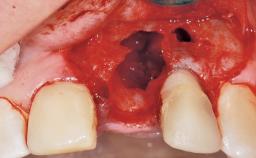

Immediate Flapless Placement of an Implant in a Maxillary Left Central Incisor Site

A 29-year-old female patient presented for treatment to replace the upper left central incisor tooth with an implant- supported restoration. The tooth had been intermittently symptomatic for the previous 12 months. The tooth had originally suffered trauma about 15 years previously. Several endodontic treatments had been performed, including an apicectomy procedure to retain the tooth. The patient was healthy and a non-smoker. She had reasonable expectations in regard to esthetic outcomes and the risk of marginal tissue recession following treatment. At medium smile, the gingival margins of the upper teeth were visible, with a display of 3 to 4 mm of the gingival margins. Gingival recession of tooth 21 and a discrepancy in the gingival levels between teeth 11 and 21 was observable during normal speech and smile.

Placement Protocol Immediate implant placement

Tooth Site Maxillary incisor or canine

Socket Morphology Single-root socket

Socket Integrity Damage to one or more bone walls

Bone Volume Damage to one or more socket walls